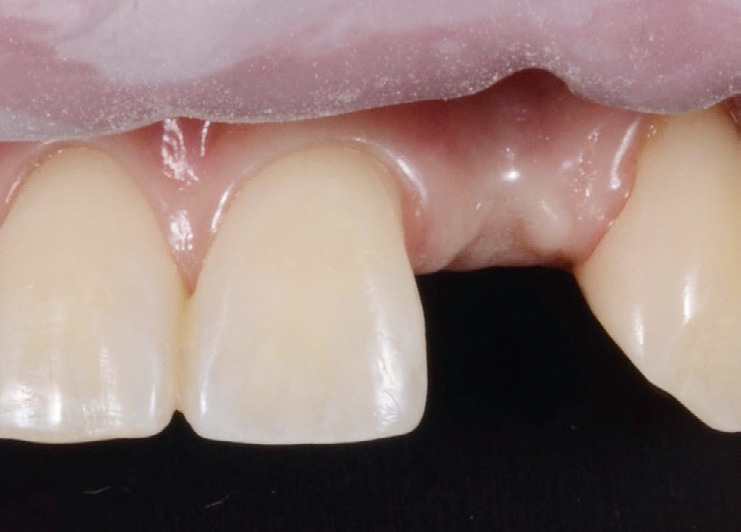

Situation after extraction with flexible retainer for pontic site development.

Pontic site developed.